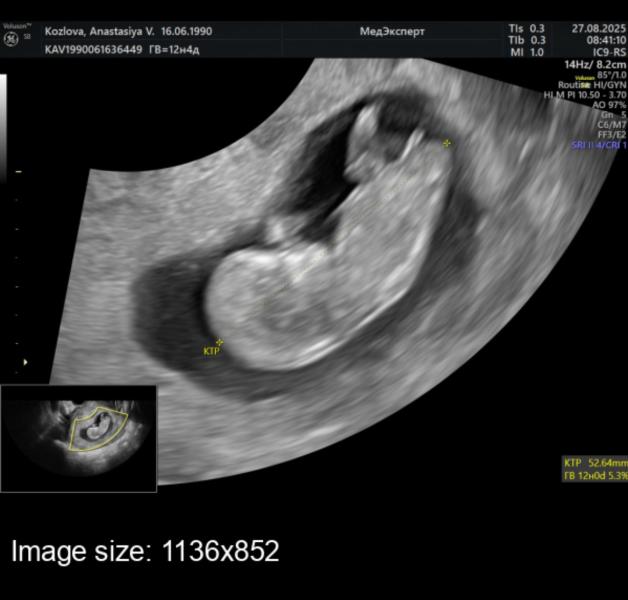

Появилось вчера немного выделений кровянистых однократно. Тк ребенок второй, то как-то уже меньше паникерства. Но и ЗБ на таком сроке тоже уже не хочется. Сходила на узи, все хорошо с человеком🙈сегодня было немного коричневых, похоже, что где-то образовалась небольшая гематома. Сестра старшая меня так нервничать не заставляла, конечно. Но и там тк ребенок был первый, нервов от врачей хватало. Зато теперь есть фото человека🥰